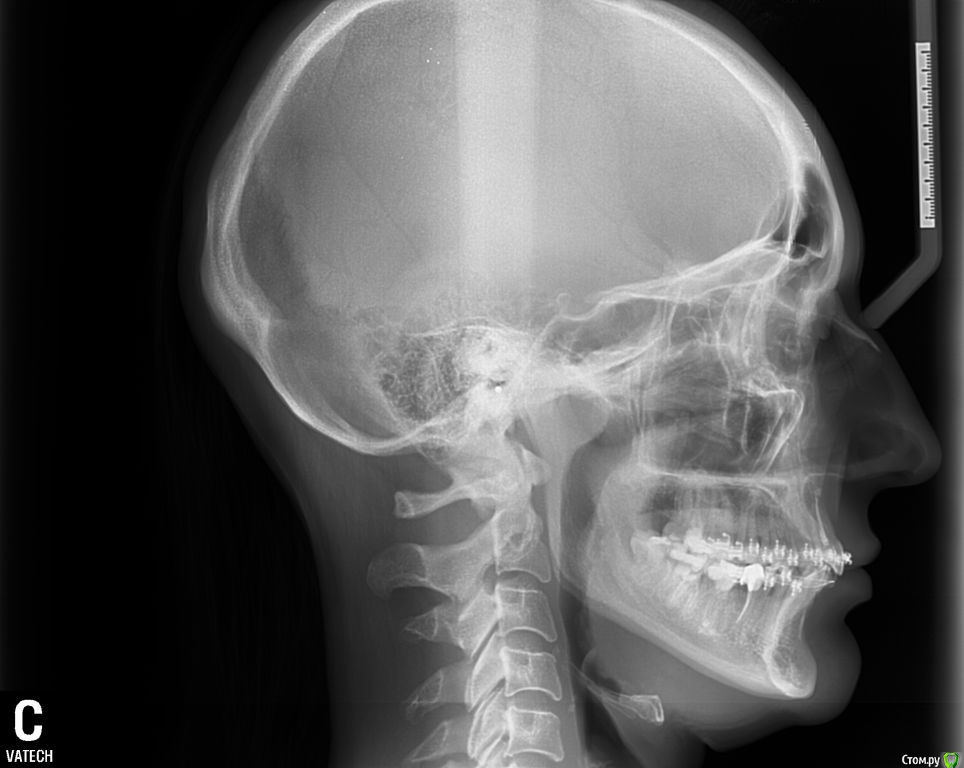

ol"ga Опубликовано 15 августа, 2015 Поделиться Опубликовано 15 августа, 2015 (изменено) Здравствуйте, Уважаемые Доктора!Очень нуждаюсь в вашей помощи. Мне 35 лет, в октябре прошлого года была установлена частичная брекет-система : на верхней ( 6 зубах, от клыка до клыка) лингвальная брекет-система и нижней ( 9 зубах) вестибулярная брекет-система и были изготовлены окклюзионные накладки на боковых зубах нижней челюсти. Перед ортодонтическим лечением никаких снимков не делала. За первый месяц ношения лингвальных брекетов верхняя челюсть достаточно быстро выдвинулась вперед, результат меня устраивал, но в дальнейшие 5 месяцев челюсть все продолжала выдвигаться вперед, в результате в прикусе впереди образовалась щель между челюстями в 5-7 мм, нижняя челюсть не так быстро успевала выдвигаться вперед, заметила что я неосознанно выдвигаю нижнюю челюсть пытаясь подстроиться под верхнюю, но речь была свистящая, шипящая, жевала на правую сторону, т.к. на левую было неудобно (по ощущениям, слева окклюзионная накладка была ниже, чем справа). Так проходила 6 мес., результат меня не устраивал, верхние зубки оставались кривыми, стали выпирать клыки, врач сказал, что это от давления дуги, а верхняя челюсть сильно выдвинулась вперед и стала похожа на открытый прикус. Мой врач сказал, что положения кривых наклонов зубов лингвальные брекеты не исправляют, а выставляют зубки в ряд, и предложил бесплатно поменять на вестибулярную брекет-систему. В конце апреля сделали панорамный снимок, трг в боковой проекции и переустановили брекет-систему на все зубки верхней челюсти, и на нижней кроме 7-к и 8-к, убрали окклюзионные накладки, но челюсть у меня не сомкнулась в привычном положении, заметила, что зубки на нижних шестерках, где были накладки, как бы просели в десну. Врач сказал, что это временно, все выровняется. Первую неделю зубки болели обычно как после активации аппарата, затем появилась боль в районе правого сустава, сначала после приема пищи, жевать я продолжала на правую сторону, пыталась приловчиться, куда удобнее, а затем боли продолжались и в покое, несколько раз просыпалась ночью от боли, пила нимесил. В этом остром периоде заметила асимметрию лица, по ощущениям нижняя челюсть «съехала» вправо, сомкнуть челюсть в таком положение не могла, сильная боль была, я ее сдвигала влево, получался перекрестный прикус (это было спустя 3 недели после установки брекет-системы). Обратилась к своему ортодонту, он сказал, что челюсть перестраивается под правильное положение зубов, могут быть боли, а асимметрию он не видит. Боли продолжались. Челюсть я так и не могла сомкнуть в « правильном» положении. Обратилась в другую клинику к ортодонту, поставили дисфункцию ВНЧС, 2 раза делала миорелаксацию с интервалом месяц (в конце мая и июня), рекомендовали не нагружать сустав и широко не открывать рот, все это я соблюдала, ела только только на левую сторону (до сих пор на нее и жую), острая боль постепенно сменилась просто дискомфортом в области правого сустава. После первой процедуры миорелаксации на второй день я смогла без боли сомкнуть челюсть в « правильном» положении, но комфортнее было ее держать в расслабленном состоянии, чуть левее, в основном я так и ходила. В это время я заметила, что у меня верхняя челюсть сместилась вправо, верхний левый зубной ряд начал мешать языку в его привычном положении, все зубки на обеих челюстях как бы наклонились в сторону языка, создалось впечатление, что челюсть сузилась. Еще постоянно царапал край дуги на верхней правой 7-е, мне ее 2 раза подпиливали и убирали щипцами, но через несколько дней опять край вылазил и накалывал щеку, решили вообще убрать замок с правой 7-и т.к. на щеке постояна была незаживающая язва от этой травмы. На днях соскочила дуга с левой верхней 7-и. Но врач сказал, что это невозможно, что воспалительный процесс в суставе он снял и я могу обратиться к своему ортодонту для продолжения ортодонтического лечения. Я обращалась еще к 5 специалистам специалистам. Никто проблемы не видит. один из специалистов в результате обследовал сделал оттиски зубов и дал заключение: Диагноз : Миофасциальный болевой синдром лица с дисфункцией височно-нижнечелюстного сустава. Дислокация диска с вправлением в левом ВНЧС.(вентральная). Бруксизм. Другой предложил шину на нижнюю челюсть, но только после снятия брекетов с нижней челюсти.Продолжаю поиски. Сделала трг в прямой, боковой и подбородочно- теменной проекции, кт обеих суставов, ищу специалистов которые могут мне помочь в моей проблеме, но в моем городе это проблема. Бруксизма за собой не замечала, родные тоже, зубами не скреплю, во сне не жую, но 100% утверждать не могу. Проблем с ВНЧС никогда не было, ни щелчков, ни хруста, ничего. На данный момент иногда поднывает в области правого сустава, а в основном чувство дискомфорта в нем. Уважаемые Доктора, подскажите, пожалуйста, как в моем случае должен проходить план лечения, можно ли исправить асимметрию лица, можно ли вернуть верхнюю челюсть на место и почему врачи не видят этой проблемы, очень нуждаюсь в вашей помощи, хочется вернуть свое лицо и функциональность внчс. Эпикриз.doc Изменено 15 августа, 2015 пользователем ol"ga Ссылка на комментарий

Skip Опубликовано 23 августа, 2015 Поделиться Опубликовано 23 августа, 2015 Вопрос по ТРГ в боковой проекции. Эти два исследования в какой промежуток времени проводились? Ссылка на комментарий

ol"ga Опубликовано 23 августа, 2015 Автор Поделиться Опубликовано 23 августа, 2015 Ровно 4 мес., там каждое фото с датой внизу, первое трг еще с лингвальными брекетами, его сделали перед переустановкой на вестибулярную брекет-систему Ссылка на комментарий